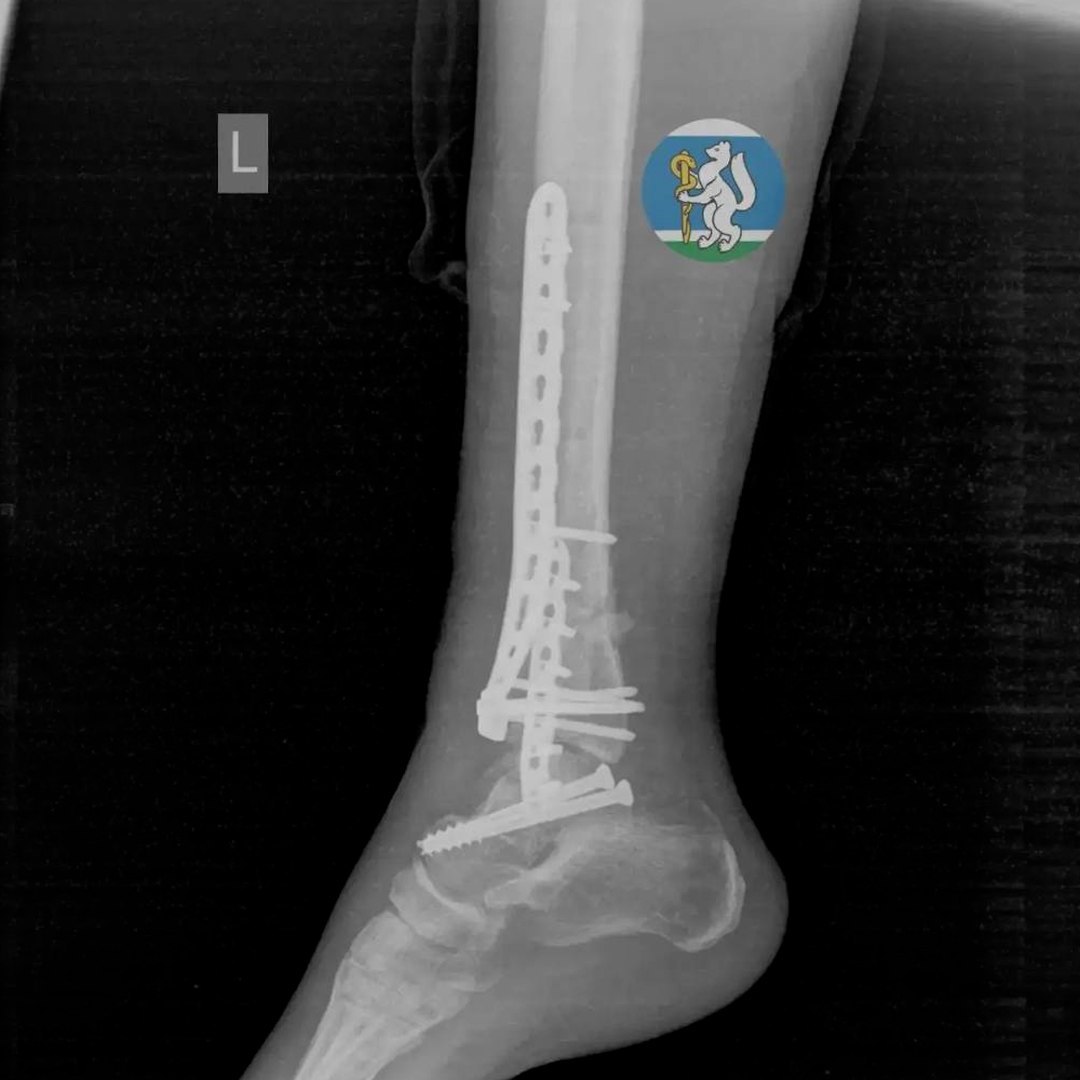

36-летняя женщина соскользнула c подоконника, когда мыла окна. Скорая забрала её с черепно-мозговой травмой, повреждением позвоночника, переломами таза и ноги.

Врачи реанимировали пациентку и провели ей несколько операций — работа шла несколько часов. Ещё месяц женщина приходила в себя в больнице. Сейчас она дома, проходит реабилитацию.